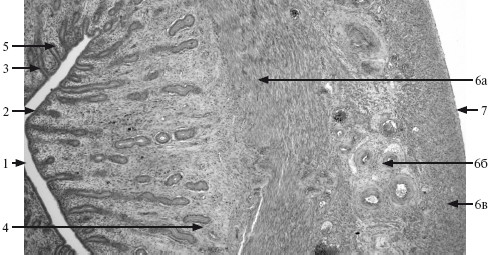

Простата снаружи покрыта тонкой капсулой из плотной волокнистой соединительной ткани с высоким содержанием ГМК. На поперечном срезе органа видны железы (простатические), которые располагаются концентрическими слоями вокруг уретры (рис. 18.2).

Рис. 18.2. Простата. ×60.

1 – уретра; 2 – переходный эпителий; 3 – слизистые (внутренние периуретральные) железы; 4 – подслизистые (наружные периуретральные) железы; 5 – главные железы (концевые отделы); 6 – пучки гладко-мышечных клеток.

Простатические железы разделяются на 3 группы:

1) слизистые или периуретральные (внутренние);

2) подслизистые (промежуточные);

3) главные (наружные).

Эпителий концевых отделов желез однорядный кубический или призматический, местами многорядный призматический. Последний содержит высокие секреторные (главные) и мелкие базальные клетки. Встречаются также отдельные эндокринные клетки.

Выводные протоки слизистых желез открываются в уретру на разных уровнях, а подслизистых и главных – по краям семенного бугорка. Секрет простаты (рН 6,5) содержит лимонную кислоту, цинк, ряд протеолитических ферментов, обеспечивающих разжижение эякулята, а также гормоны (простагландины).